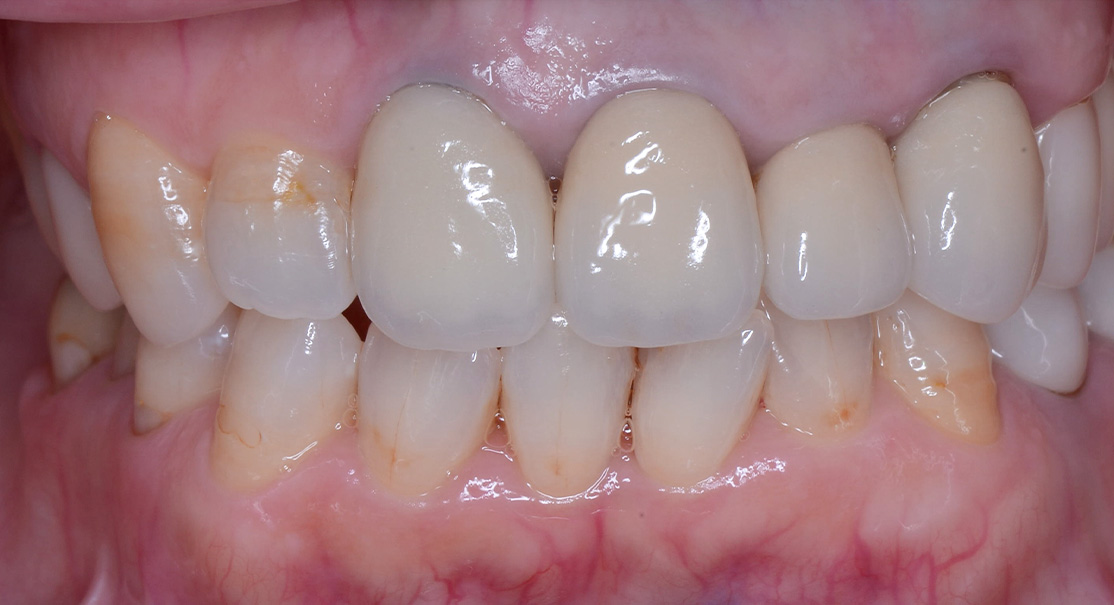

主訴 前歯が折れた 全体的に診てほしい

問題点

・20年以上歯科医院に行かず虫歯を放置していた。

・歯科治療に対し恐怖心があった。

治療計画

・虫歯を長期間放置していたため、審美障害、咬合平面の崩壊、顎位の偏位、臼歯の舌側傾斜、歯周病の罹患等々様々な問題が生じていました。

・患者様にはまず虫歯の治療、歯周病の治療を行い、最終的にクラウン等で歯冠修復が必要という説明をさせて頂きました。

主訴 前歯が折れた

全体的に診てほしい